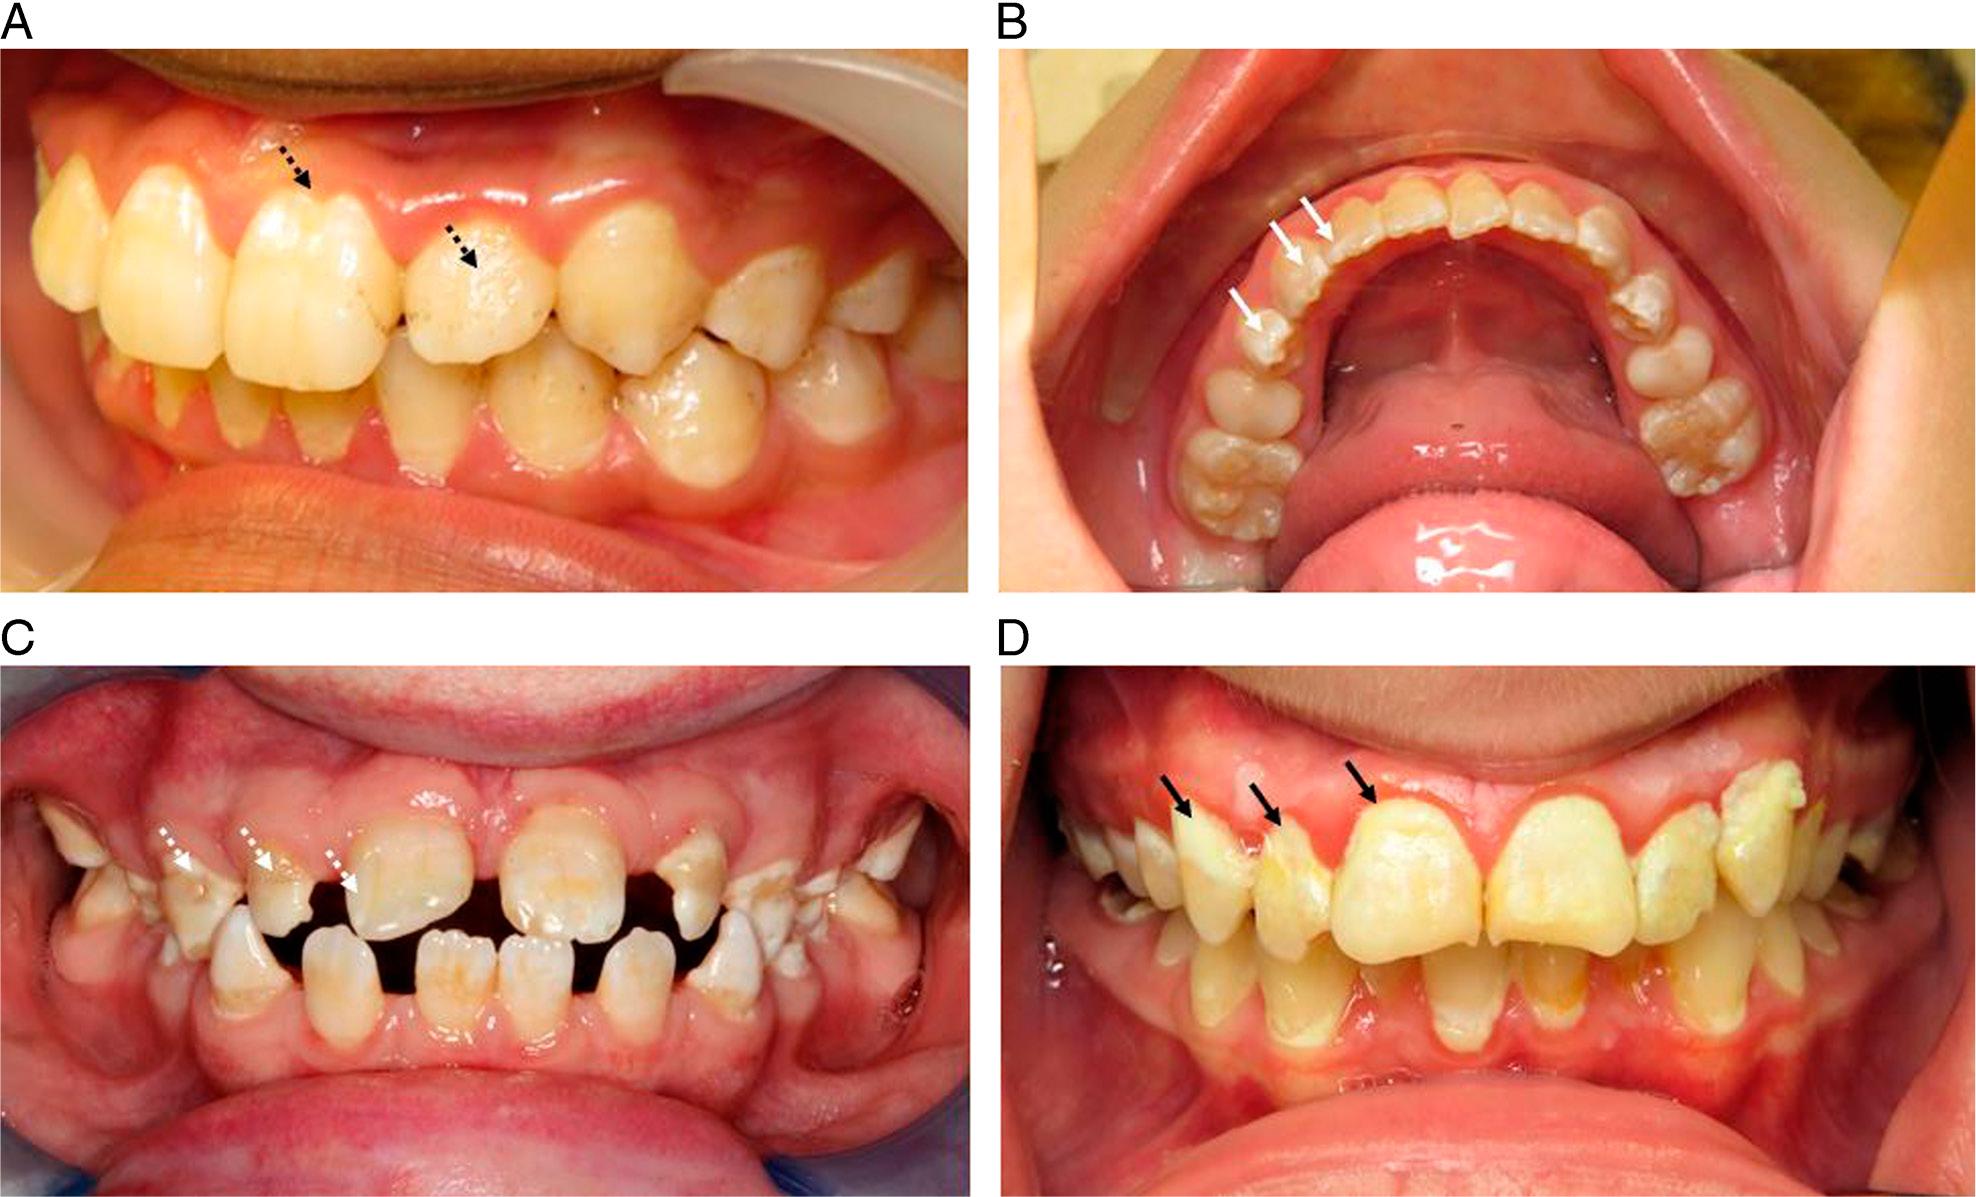

Caution is required to ensure that enamel hypoplasia is not erroneously diagnosed as MIH. Enamel hypoplasia is a quantitative enamel defect (Figure 2a) and results from systemic and/or local impacts during formation of the enamel matrix and the tooth’s maturation phases.44

Clinical photographs of (A) hypoplastic quantitative defect on the upper left central incisor and diffuse defect across all other maxillary teeth (black dashed arrows), (B) fluorosis with diffuse, opaque defects (white arrows) affecting all of the lower permanent dentition, (C) amelogenesis imperfecta with diffuse areas of white and brown defects (white dashed arrow) affecting all permanent dentition, (D) white-spot caries lesions at the gingival margins of multiple teeth (black arrows).

Several conditions may present with tooth hypomineralisation and so care is required to accurately diagnose MIH from other DDE such as fluorosis, amelogenesis imperfecta, white spot lesions and traumatic hypomineralisation. Fluorosis is related to fluoride ingestion during amelogenesis and usually presents as diffuse, uniformly distributed enamel opacities (Figure 2b). The primary dentition remains unaffected whilst multiple permanent teeth tend to be involved, without the typical pattern of molars and incisors as seen with MIH. Amelogenesis imperfecta is a heterogenous group of conditions resulting in qualitative and quantitative defects, with 10 different genetic codes identified for the multiple phenotypes (Figure 2c).45

There will often be a family history of the condition and most of the primary and permanent teeth are affected. White spot carious lesions can appear chalky, matt and opaque compared to adjacent healthy enamel but typically arise in regions of plaque accumulation such as the adjacent the gingival margin of the teeth (Figure 2d). Traumatic hypomineralisation can occur when the developing permanent tooth germ is impacted following trauma to the primary predecessor.